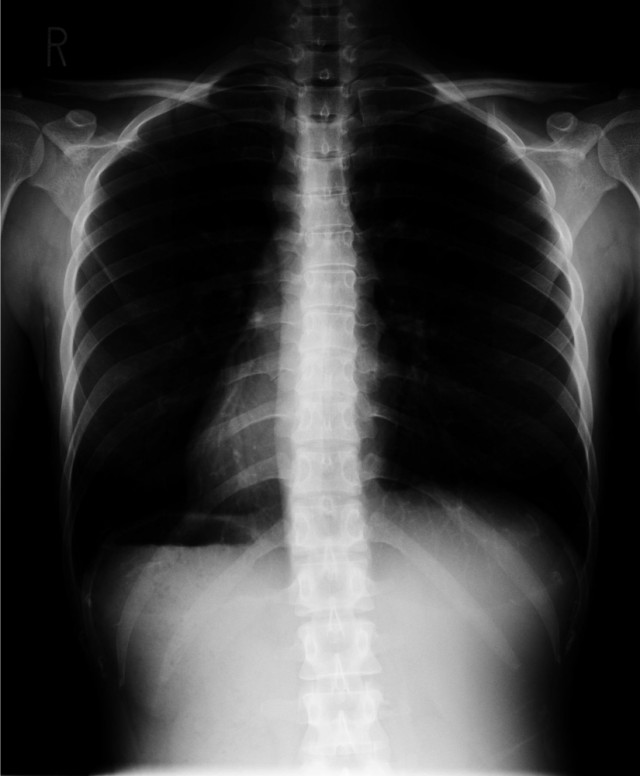

正面像

【内容】

・頸椎正面像(開口像)、頸椎側面像

・胸椎正面像、胸椎側面像

・腰椎正面像、腰椎側面像

- 背骨のカーブや骨盤の歪みを確認するため

- 椎間板の厚みや骨の変形を確認するため

- どこの骨を矯正するか正確に判断するため

- 先天的に奇形や病理的なものを見つけるため